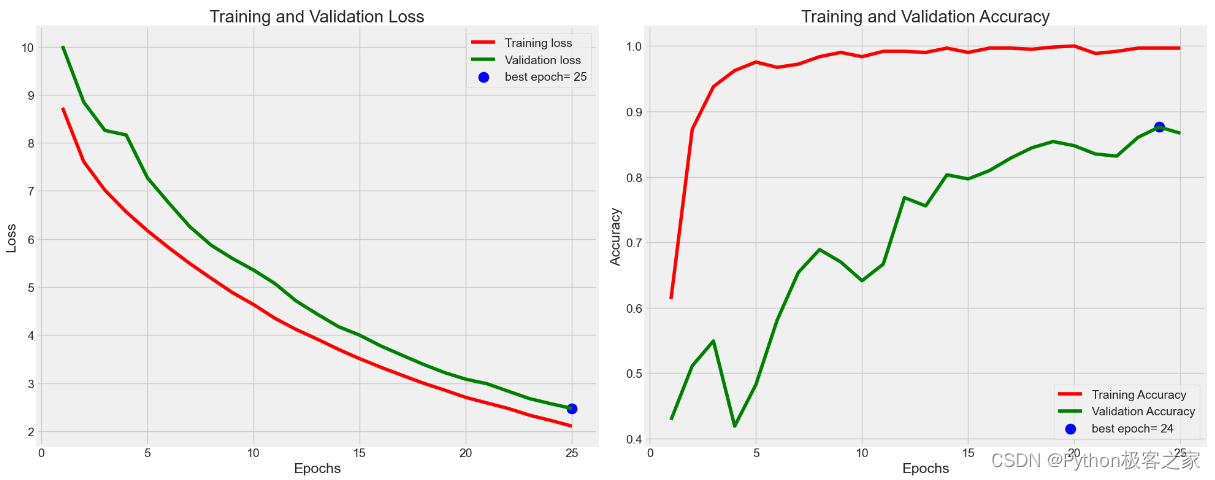

5. 模型预测评估

利用训练集和验证集完成模型的训练和验证后,利用测试集进行预测评估,测试集预测准确率达到 90.28%

print("Test Accuracy: ", test_score[1])Train Loss: 2.6708874702453613 Train Accuracy: 1.0 -------------------- Validation Loss: 3.06054425239563 Validation Accuracy: 0.8500000238418579 -------------------- Test Loss: 2.887510299682617 Test Accuracy: 0.9027777910232544